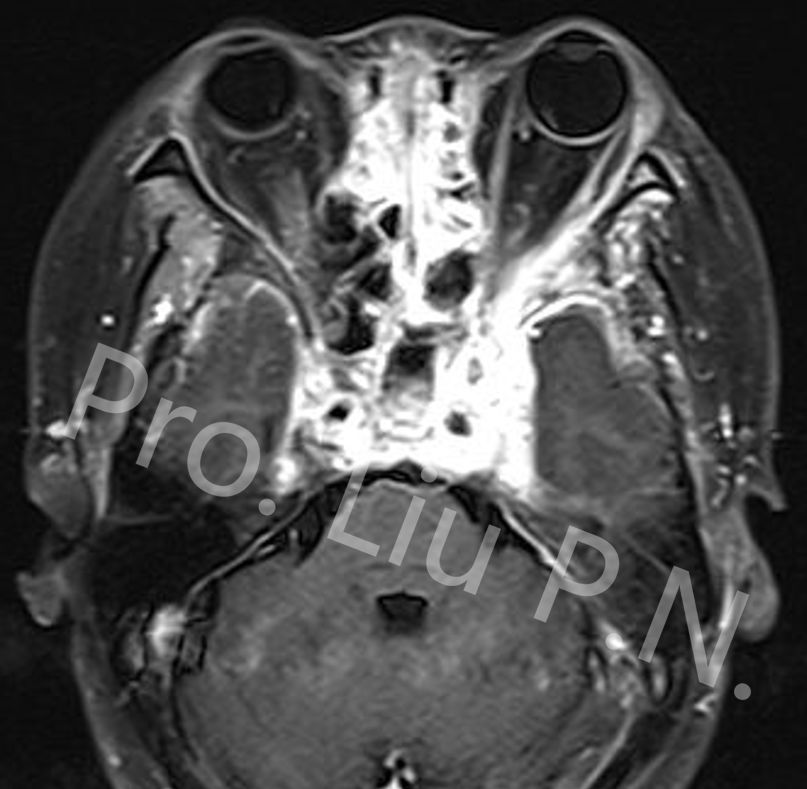

十三、经眶外侧壁入路内镜解剖

![]()

左眼眶皮肤切口

向内侧牵开眶内容物

磨除眶外侧壁

切除颞极前方硬膜